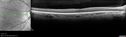

fovealaplasia_demc_030615_02.jpg

Foveal hypoplasia - aplasia451 x angesehenSD OCT shows persistent plexiform layers in the center of the macula